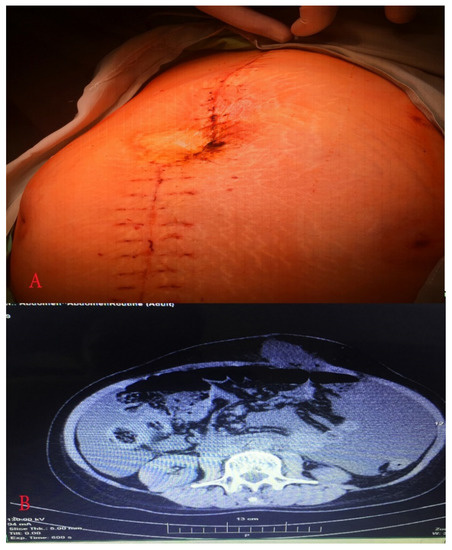

2. Case Report